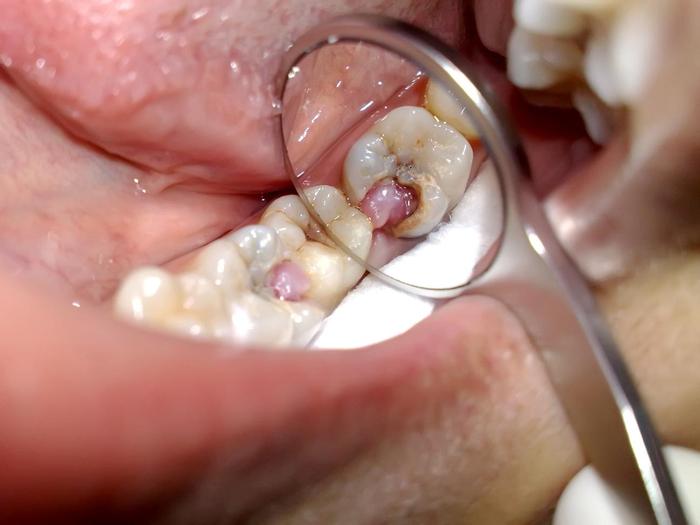

非常深的蛀洞穿过牙釉质,一直穿过牙釉质直到牙髓。然后细菌引起牙髓炎症。身体试图抵抗细菌越多,牙齿内的压力越高,直到压力可能会扼杀血管并导致牙髓死亡。